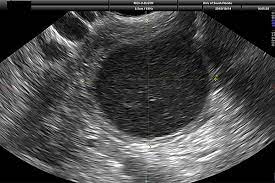

While ovarian cancer has the lowest survival rate for all cancers, 92 per cent of patients will. Type of ovarian cyst that can turn into cancer it's the dermoid cyst, also called a teratoma or mature cystic teratoma (mct). He doesn't think my reflux problem is related to my pelvic pain. Ovarian cysts of less than 1 centimeter (0.4 inches) in size are common in postmenopausal women, the vast majority of which will be benign. These benign cysts originate from germ or embryonic cells and thus contain different kinds of tissue such as cartilage, bone and skin.

Ovarian cancer and cysts have similar symptoms and signs, for example, pain during intercourse, pelvic pain, and urinary problems. After pleading with one doctor to finally listen to her, she got a much more. Mature cystic teratomas, also called dermoid cysts, rarely undergo a malignant transformation, i.e. Yesturday i had keyhole surgery to remove what they thought was just a normal 6cm cyst on my right ovary. Ovarian cancer starts in the cells lining the ovaries. Every year, 7,000 women are diagnosed with ovarian cancer and 4,300 women lose their lives to it. Malignant ovarian cysts are only seen in rare cases, with the benign being the most common of them all. These benign cysts originate from germ or embryonic cells and thus contain different kinds of tissue such as cartilage, bone and skin. However, as women, this is something we need to be talking about. What is dermoid ovarian cyst? The largest type of ovarian cyst is called a cystadenoma. Her surgery was due to multiple painful complex cysts on her uterus. This is one of the main reasons why ovarian cancer is so difficult to detect at an early stage.